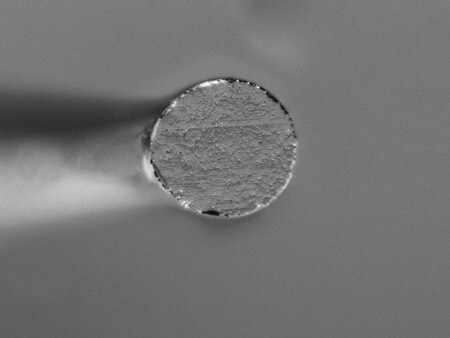

Beispiele für die Erfassung und Betrachtung von Kathetern

Die Bildzusammensetzungsfunktion ermöglicht die Betrachtung über ein breites Sichtfeld mit hoher Auflösung.